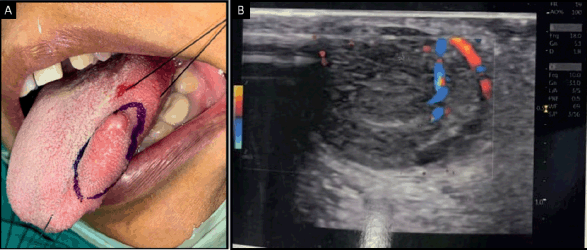

Ultrasonography of the tongue revealed a solid-appearing, mildly heterogenous lesion with smooth margins and vascularity within it, which was suggestive of a vascular malformation. Plain and post-contrast magnetic resonance imaging of the tongue revealed a well-defined ovoid T2-weighted hyperintense lesion, which appeared isointense on T1-weighted imaging and was suggestive of a cystic lymphangioma of the tongue (Figure 1). No abnormality was detected on computed tomography of the chest and abdominal ultrasound.

Figure 1. (a): Intraoral photograph showing swelling on the left lateral border of the tongue. (b): Ultrasonography of tongue showing mildly heterogenous lesion with smooth margins and vascularity.